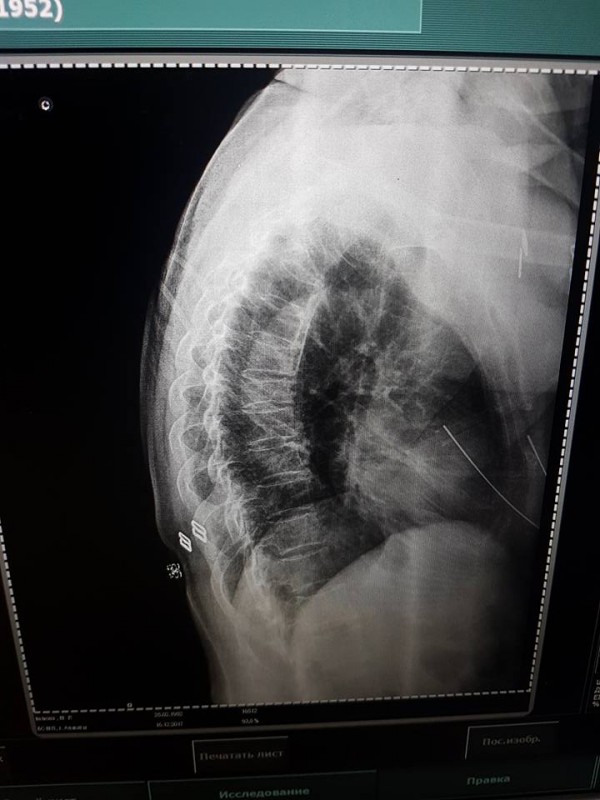

"В тяжелом состоянии доставили в БСМП, провели обследование, сделали МРТ. Закрытая черепно-мозговая травма, ушиб грудной клетки, компрессионный перелом позвоночника (7 позвонок). Требуется операция на позвоночник", - написала девушка.

Фото©Дина Нарбаева